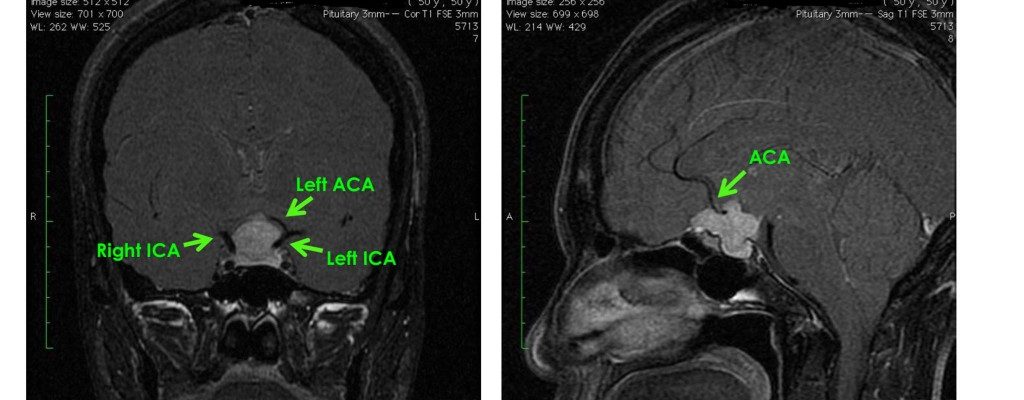

在中國的MRI顯示在顱底骨基部有2厘米的腫瘤,向腦上延伸和壓迫著視覺神經,在兩側亦包住雙側腦內主大動脈(ICA)和前大腦動脈(ACA)。

最後於香港私家醫院做6小時了的微創顯微開顱手術,腫瘤全面切除。視覺神經得到減壓, 雙側腦內主大動脈(ICA)和前大腦動脈(ACA)保存完好。視力恢復正常。 手術後3天送返回中國內地。